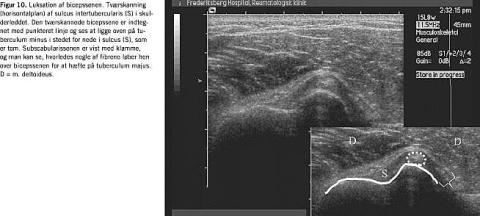

Også mere usædvanlige diagnoser som luksation af bicepssenen kan stilles på baggrund af UL-undersøgelse (Fig. 10 ).